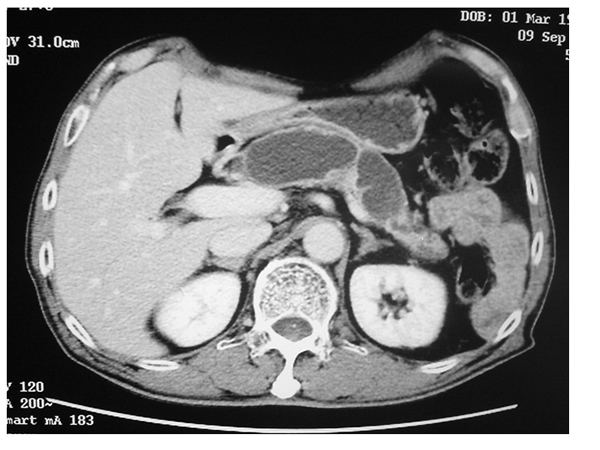

Müsinöz Kistik Neoplazi

Bu kist tipide ağırlıklı olarak kadın cinsiyetinde görülür. Genellikle 50’li yaşlarda saptanır. Hemen tamamı pankreasın gövde ve kuyruk bölgesinde yerleşir. Kansere dönüşme potansiyelleri nedeniyle tanı konulduğunda cerrahi tedavi önerilir.